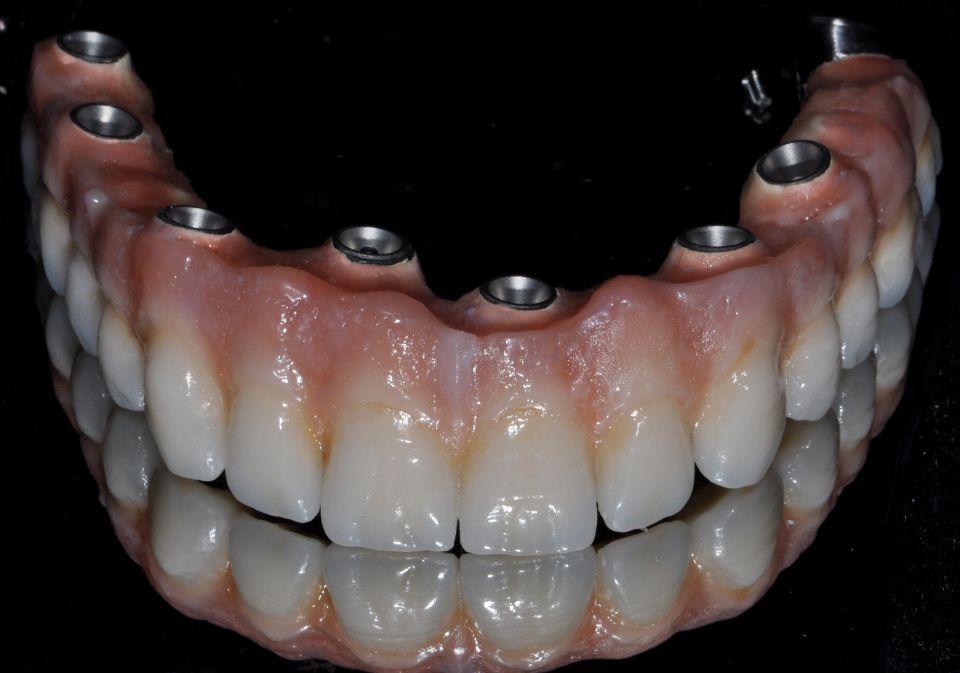

Prosthetic rehabilitation

Oral rehabilitation is the part of dentistry that is concerned with restoring oral aesthetics and harmony through dental prostheses, always looking for a correct occlusion and function. It integrally combines the areas of fixed prosthesis, removable prosthesis, operative, occlusion and dental implant.

When carrying out the treatment plan, appropriate to the patient, an attempt will be made to recover their oral health through the most modern rehabilitation techniques; establishing a close relationship with the other disciplines of dentistry, such as periodontics, endodontics and orthodontics. To achieve the best result.

By means of current dental techniques, it is possible to carry out these restorations by means of fixed prostheses on teeth or dental implants in more than 95% of patients, thus avoiding the use of removable prostheses that are always uncomfortable and in many cases impossible to bear.

One of the techniques most used today thanks to technological advances, is digital oral rehabilitation or digital flow.

Rehabilitation with digital flow

Through 3D digital impressions we carry out much more perfect and adapted prosthetic restorations from the first day, since the precision of the work is much higher, obtaining predictable results.

They can be performed both on crowns on natural teeth and on implants, giving patients greater comfort and ease.